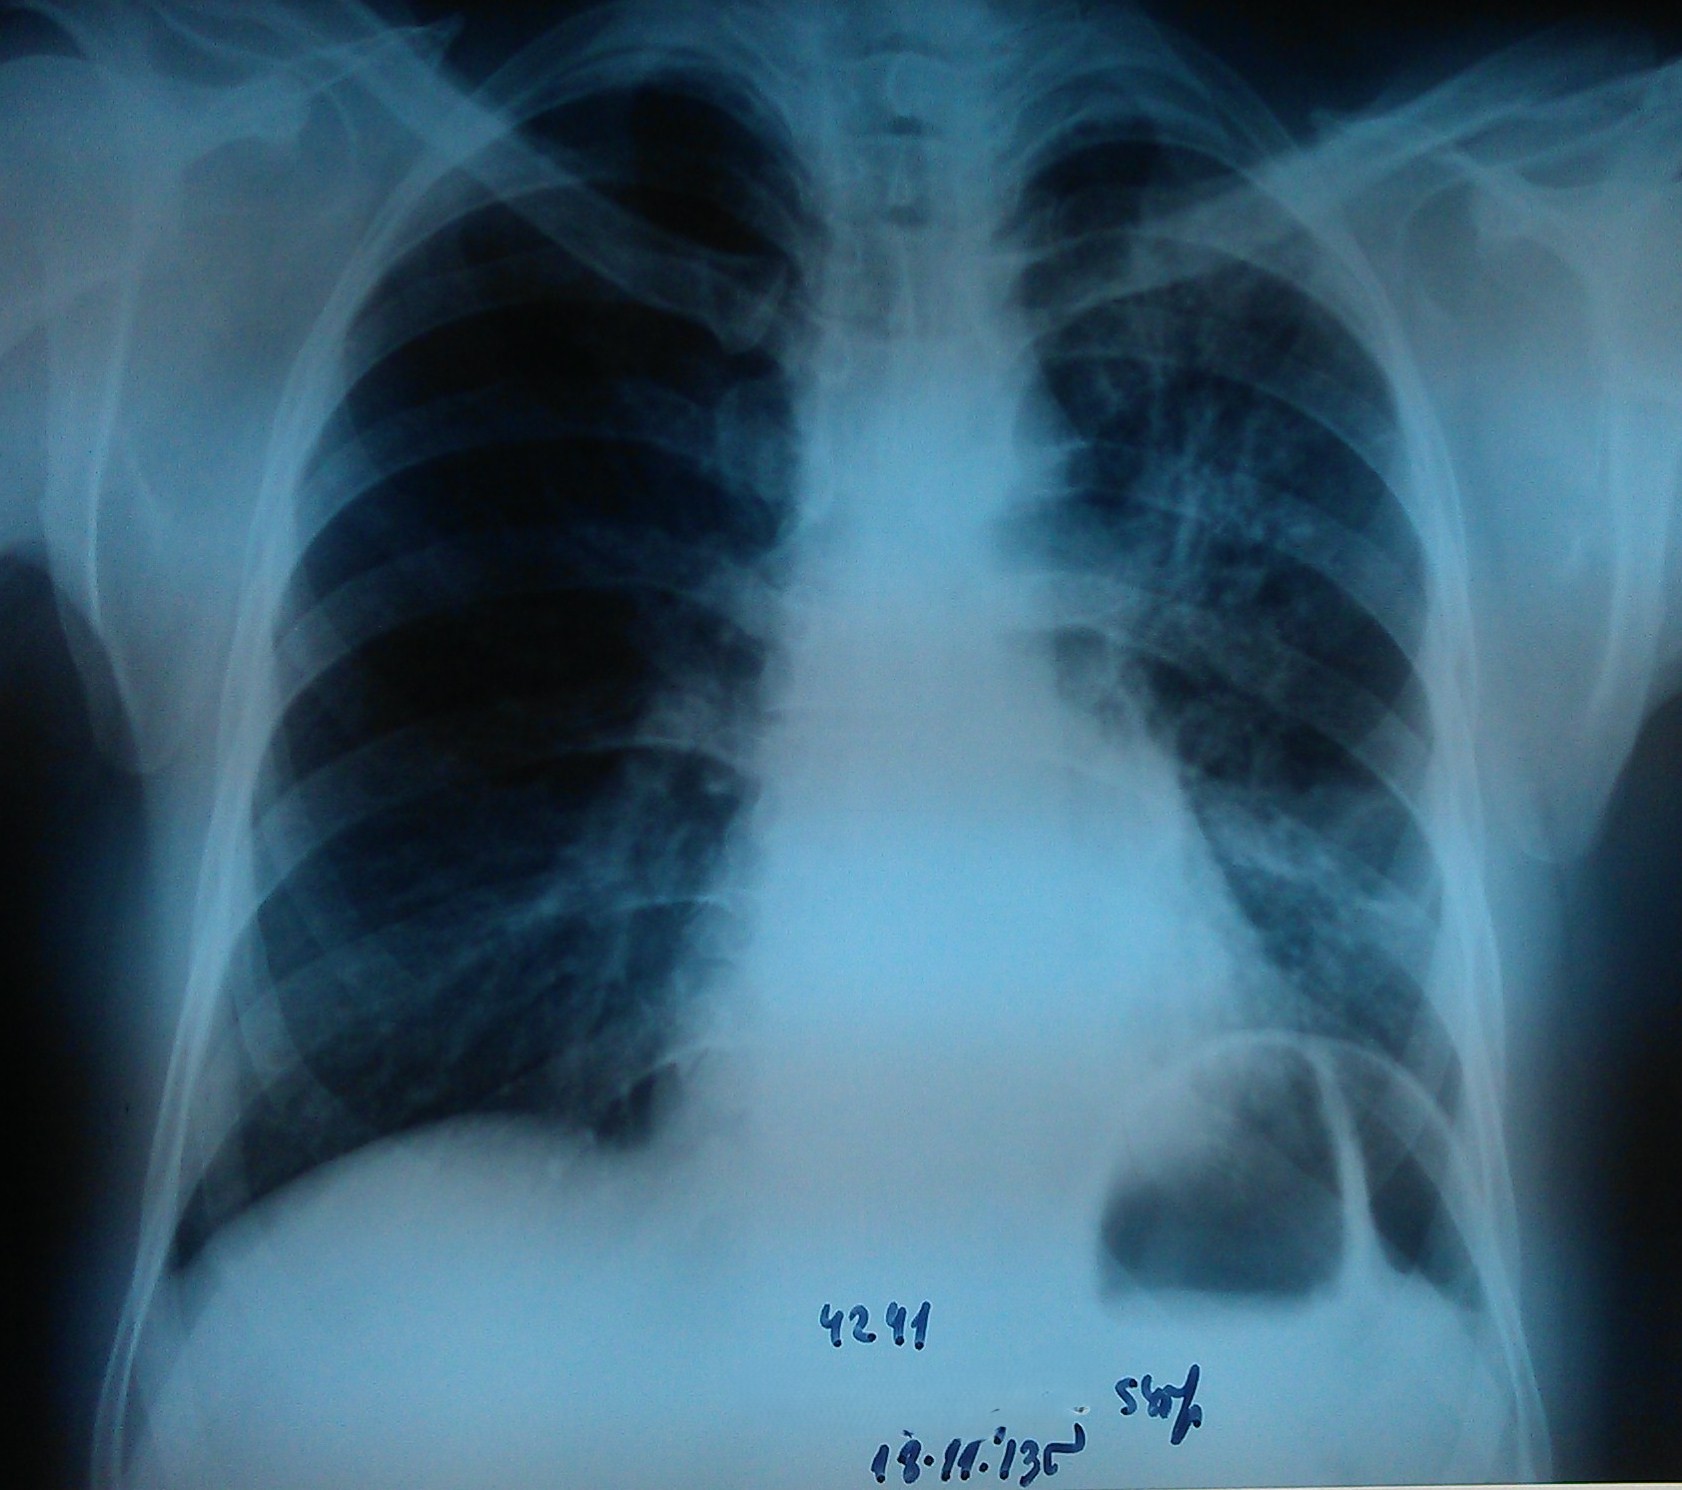

- გულმკერდის რენტგენოგრაფია რეზექციიდან 4 დღის შემდეგ

მარცხენა ფილტვი თითქმის მთლიანად გაშლილია.